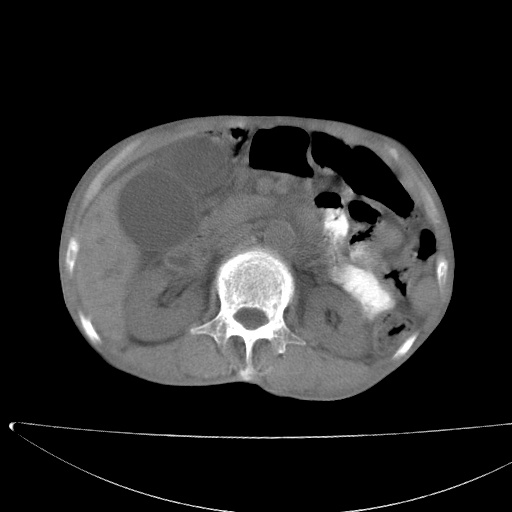

标题: CT17147:男70岁,上腹部不适1月。 [打印本页]

患者男70岁,上腹部不适1月。8年前有胃癌手术史。余病史不祥。

考虑胃癌复发并小网膜淋巴结转移侵及肝脏胆总管梗阻

考虑胃癌复发并腹腔内淋巴结转移。

考虑胃窦癌肝门转移

考虑胃窦癌肝门区淋巴结转移!